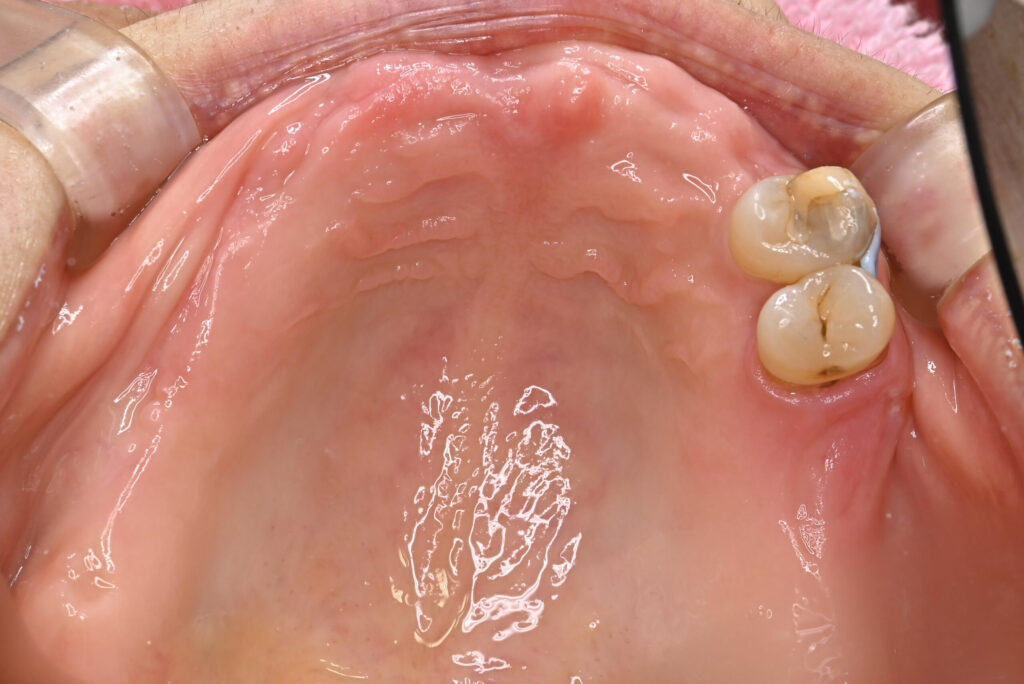

Before

治療期間・回数

約6ヶ月・約6回

費用

23,100,000円

治療のリスク

外科手術が必要になるため、患者様に体力的な負担がかかる。